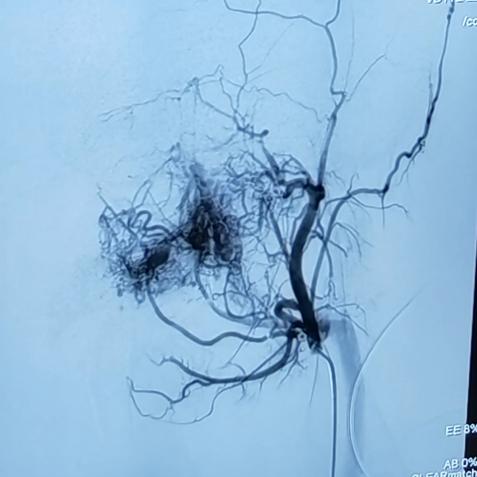

3.数字减影血管造影(digital subtraction angiography,DSA)检查可以相对全面地反映颌骨中心性血管瘤的血管构筑及血流动力情况,可以作为颌骨中心性血管瘤动诊断的“金标准”,典型表现为具有动静脉瘘口的畸形血管团块、扩张的供血动脉及静脉期提前显示的回流静脉。

左下颌中心性血管瘤DSA表现畸形的血管团块